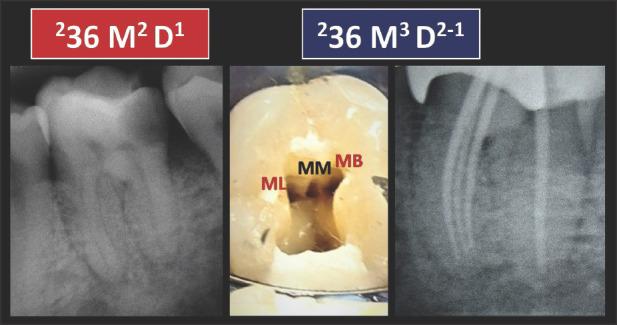

应用根管解剖分类新系统于临床实践:说明与详述。

Application of a new System for Classifying Root and Canal Anatomy in Clinical Practice - Explanation and Elaboration.

Adequate understanding and accurate characterization of normal and unusual root and canal morphology are essential requirements for successful root canal treatment. A new coding system for classifying root and canal morphology, accessory canals and anomalies has been introduced. In addition to technological advances related to experimental studies involving micro-computed tomography, the continuing clinical advances in magnification, illumination, imaging and intra-operative root canal treatment procedures have allowed clinicians to identify an increasingly wide range of anatomical variations in roots and canals in an attempt to achieve more predictable clinical outcomes. This review aims to provide a step-by-step explanation for the clinical application of the new coding system in dental practice, and to describe the anatomical variations in roots and canals for teeth scheduled for root canal treatment.

充分理解和准确描述正常和异常的牙根和根管形态是根管治疗成功的基本要求。引入了一种新的根管形态、副根管和异常分类编码系统。除了与涉及微计算机断层扫描的实验研究相关的技术进步外,放大、照明、成像和术中根管治疗程序的持续临床进展使临床医生能够识别越来越广泛的根和根管的解剖变异,试图实现更可预测的临床结果。本综述旨在为新编码系统在牙科实践中的临床应用提供逐步解释,并描述计划进行根管治疗的牙齿的牙根和根管的解剖变异。